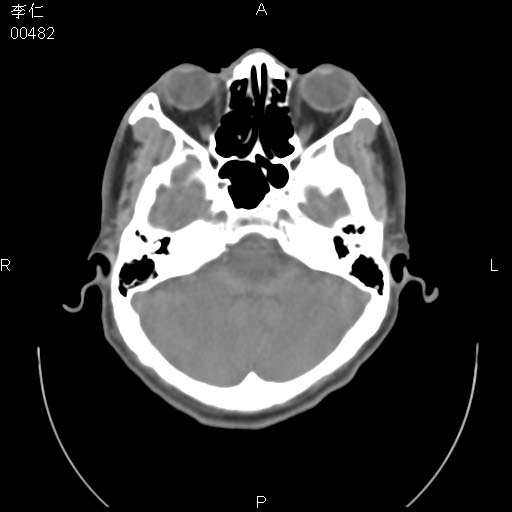

患者男,45岁。于二月前发现左眼稍肿,去看眼科,查肾功(—),来查ct,我看到的是左侧上眼睑内低密度影,ct值是-600到-700hu。

是一个副鼻窦的正常变异,脂肪瘤的密度不可能这么低,-600到-700.

只是空气而已,属正常ct表现。

正常表现,眼睑与结膜zhi间的空气

正常,为结膜囊内气体。

左侧眼球壁光滑,未见异常密度灶,眶内结构清晰,眼内肌、视神经均正常。所见低密度灶,本人考虑:1、五官科翻上睑造成;2、炎症(产气细菌感染)。